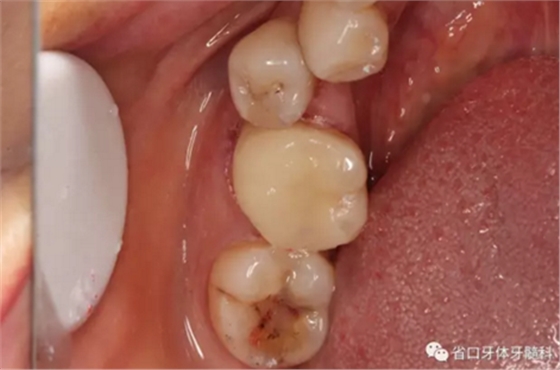

圖4 牙體預備后頰側觀